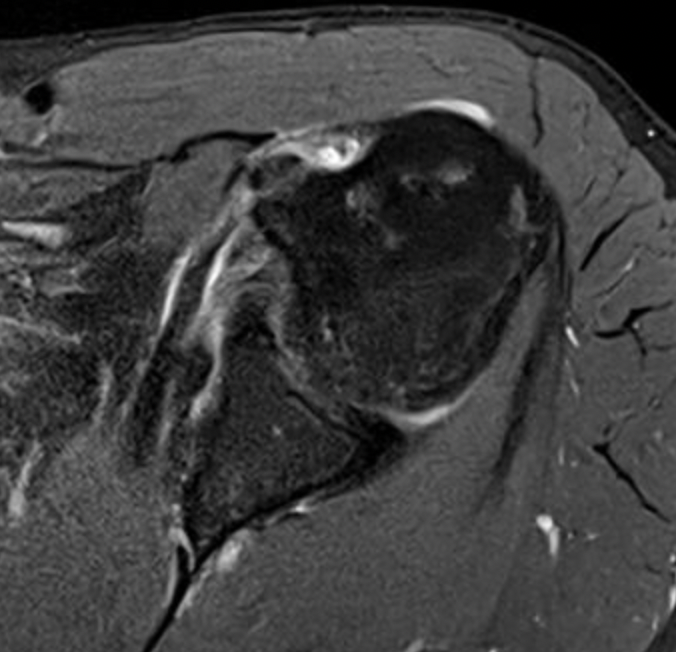

Medial subluxation with subscapularis tear